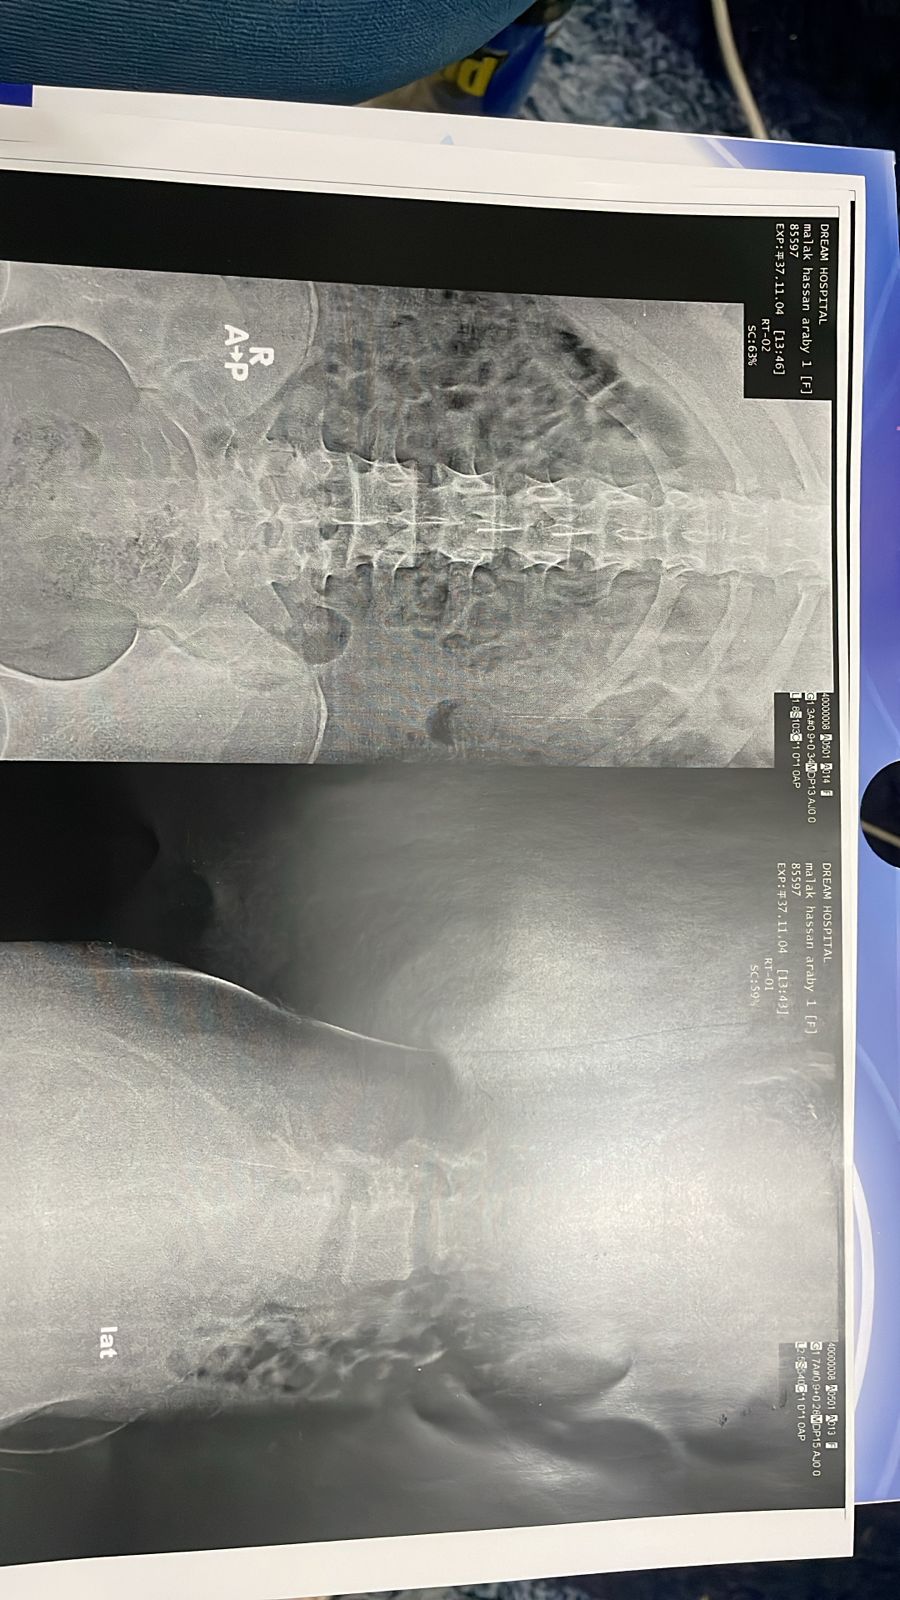

الأشعة الطبية للفتاة

وأوضحت السيدة أن الفتاة نُقلت إلى المستشفى، حيث خضعت لعدد كبير وغير مبرر من الفحوصات، من بينها أشعة على الفقرات والقطنية وأخرى مقطعية، دون إعطائها أي مسكنات.

وتابعت بأنه كان من المفترض البدء بأشعة عادية، ومن ثم استدعاء المزيد من الإجراءات في حالة تطلب الأمر.

وأبدت السيدة استياءها من إدراج مزيد من الفحوصات داخل الفاتورة دون داعٍ، على حد تعبيرها، موضحة أنها فوجئت بمحاولة إجراء أشعة على البطن رغم أن الإصابة كانت في الكتف.